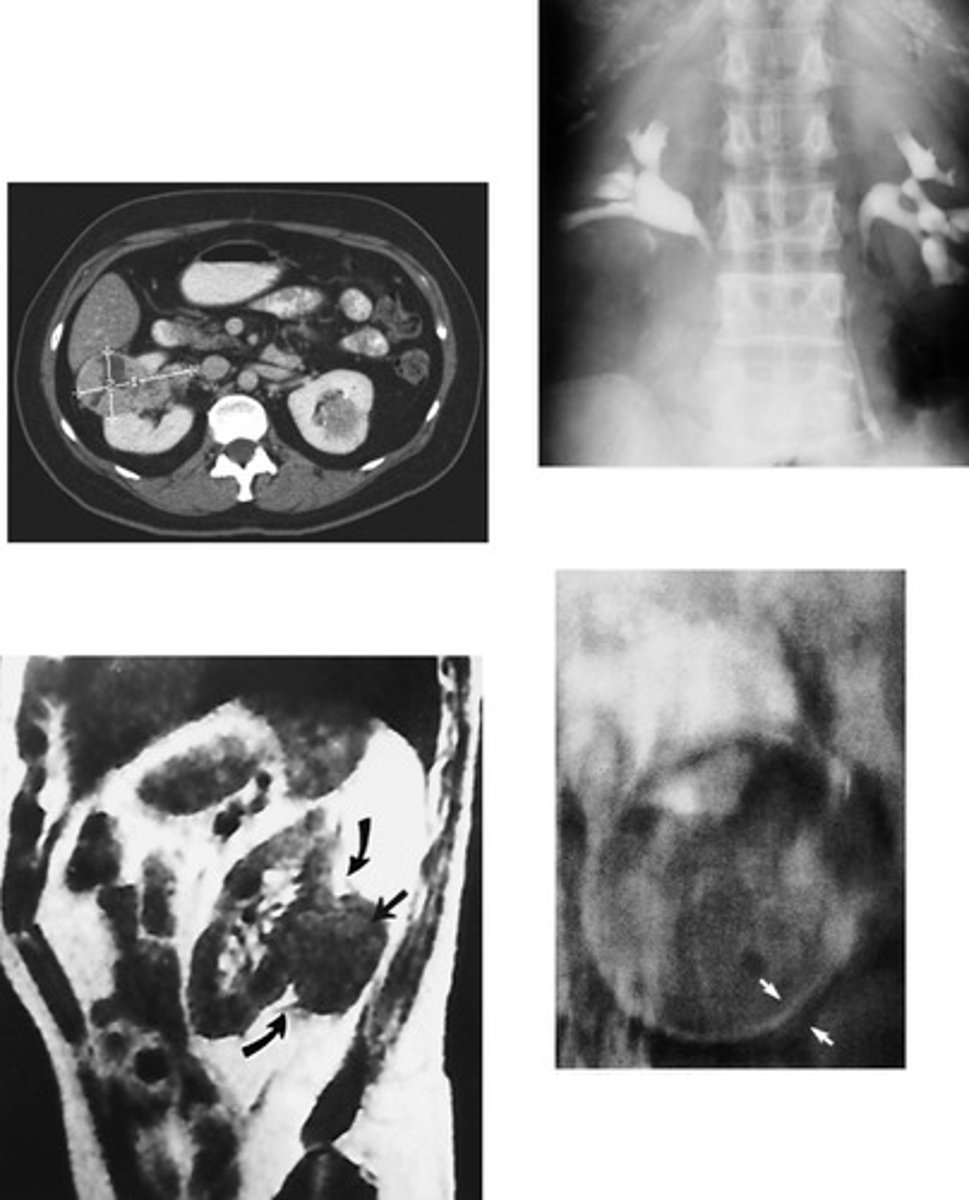

- Wilms Tumor / Nephroblastoma

- Infants and children

- What type of renal neoplasm arises from the embryonic renal tissue that distorts the calyces and creates a vine like blood supply?

- This is the most common abdominal neoplasm in who?

- Neuroblastoma

- second / children

- What type of abdominal neoplasm arises from the adrenal gland (endocrine system) and pushes down on the kidney?

- This is the _________ most common abdominal neoplasm in whom?